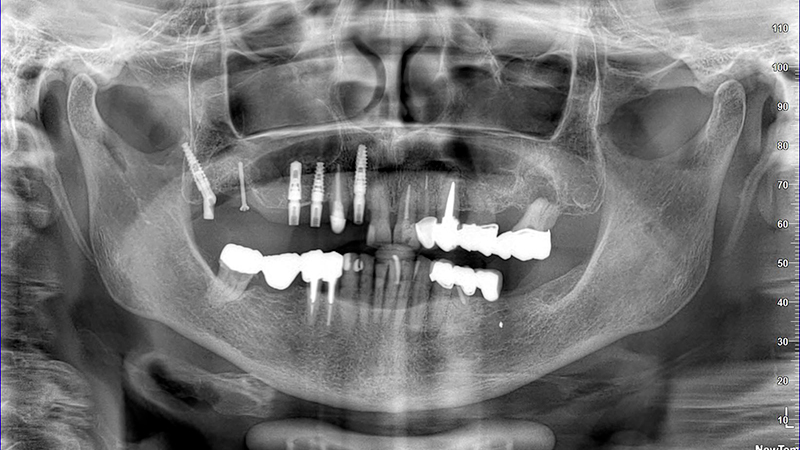

La paziente, di 68 anni, buona salute generale, presentava un grave problema al ponte 17-15-14 con dolore alla masticazione, mobilità e grave perdita ossea su 17 e 12 (Figs. 1, 2, 3).

OPT con pterigoideo 17, rialzo trans-crestale 15 e Socket Shield su 12 e applicazione monconi per le conometrie protesiche parallele

Fig. 15 - OPT con pterigoideo 17, rialzo trans-crestale 15 e Socket Shield su 12 e applicazione monconi per le conometrie protesiche parallele

Fig.  16, 17, 18 - OPT con pterigoideo 17, rialzo trans-crestale 15 e Socket Shield su 12 e applicazione monconi per le conometrie protesiche parallele

La finalizzazione del caso avveniva con protesi in metallo-ceramica passivata su cappe conometriche in bocca (Figs. 24, 25, 26, 27, 28, 29, 30, 31, 32) e radiografie finali ad un anno dal carico (Figs. 33, 34).

Figs. 32, 33, 34 - Radiografie finali impianti 17, 15, 14 ad un anno dal carico con guarigione del rialzo di seno trans-crestale del 15, impianto pterigoideo 17 e Socket Shield 12